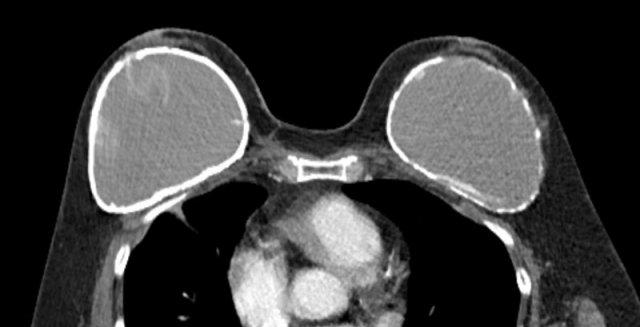

Trên hình CT cắt ngang này, có hình ảnh dày bao xơ kèm vôi hóa bao xơ nặng nề.

Ở bên phải, ngoài ra còn thấy hình ảnh nội dung không đồng nhất và một số đường thẳng dạng tuyến, gợi ý vỡ túi trong bao xơ.